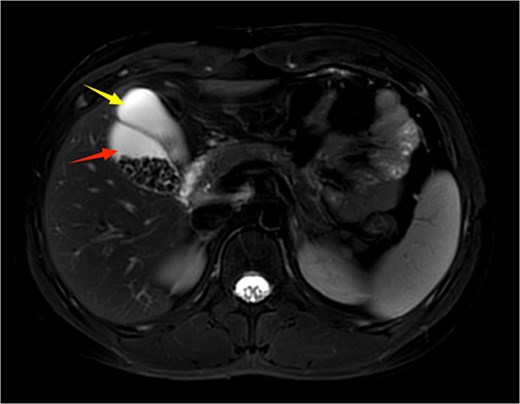

A 21-year-old male patient was admitted to our hospital with a 2-year history of intermittent right upper quadrant colicky pain. The symptoms initially occurred 2 years ago after consuming fried food, accompanied by nausea and vomiting, and were relieved after antispasmodic and analgesic treatment. Over the past 2 years, the symptoms recurred frequently, prompting the patient to seek further evaluation at our institution. The patient had no significant past medical history, including hypertension, diabetes, coronary heart disease, or other chronic conditions. He denied smoking, alcohol consumption, and any known drug allergies. Physical examination on admission revealed stable vital signs, with no jaundice observed in the skin or sclera. The abdomen was flat, with mild tenderness in the right upper quadrant and no rebound tenderness. The liver and spleen were not palpable. Murphy's sign was negative, abdominal percussion yielded tympanic sounds, and bowel sounds were normal. Laboratory tests, including complete blood count, liver function (bilirubin, ALT, AST, etc.), coagulation profile, amylase, lipase, and infection markers, were all within normal limits. Ultrasonography indicated multiple gallstones, a thickened and indistinct gallbladder wall, and suspicion of a folded gallbladder or possible double gallbladder malformation. To further delineate the biliary anatomy and ensure surgical safety, an abdominal MRI was performed. Magnetic resonance imaging (MRI) confirmed a double gallbladder malformation, with multiple stones in the lateral gallbladder (Figs 1 and 2). The clinical diagnosis was established as cholelithiasis with double gallbladder malformation.

Upper abdominal MRI coronal view demonstrates a double gallbladder variation. The two arrows indicate the respective gallbladders, the lateral one of which contains multiple gallstones.